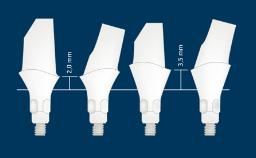

O projeto de todas as próteses sobre implante deve ser baseado em um plano protético e deve abordar todos os fatores de planejamento específicos identificados como relevantes. Há vários aspectos que são comuns ao planejamento da maioria das próteses fixas sobre implante (ou PFs), e é útil organizar esses pontos em uma sequência lógica de planejamento. O primeiro ponto é a seleção do tipo e configuração da PF. O próximo ponto é a seleção do método de retenção, seguido da consideração dos aspectos externos e da estrutura interna necessária para abordar fatores como estética, função e força. Este módulo examinará cada um desses pontos de planejamento, por sua vez. Os Módulos de Aprendizado da Academia, mais detalhados e separados, baseiam-se no presente Módulo e abordam a seleção de materiais restauradores para a PF, a seleção de pilares e a configuração dos implantes.